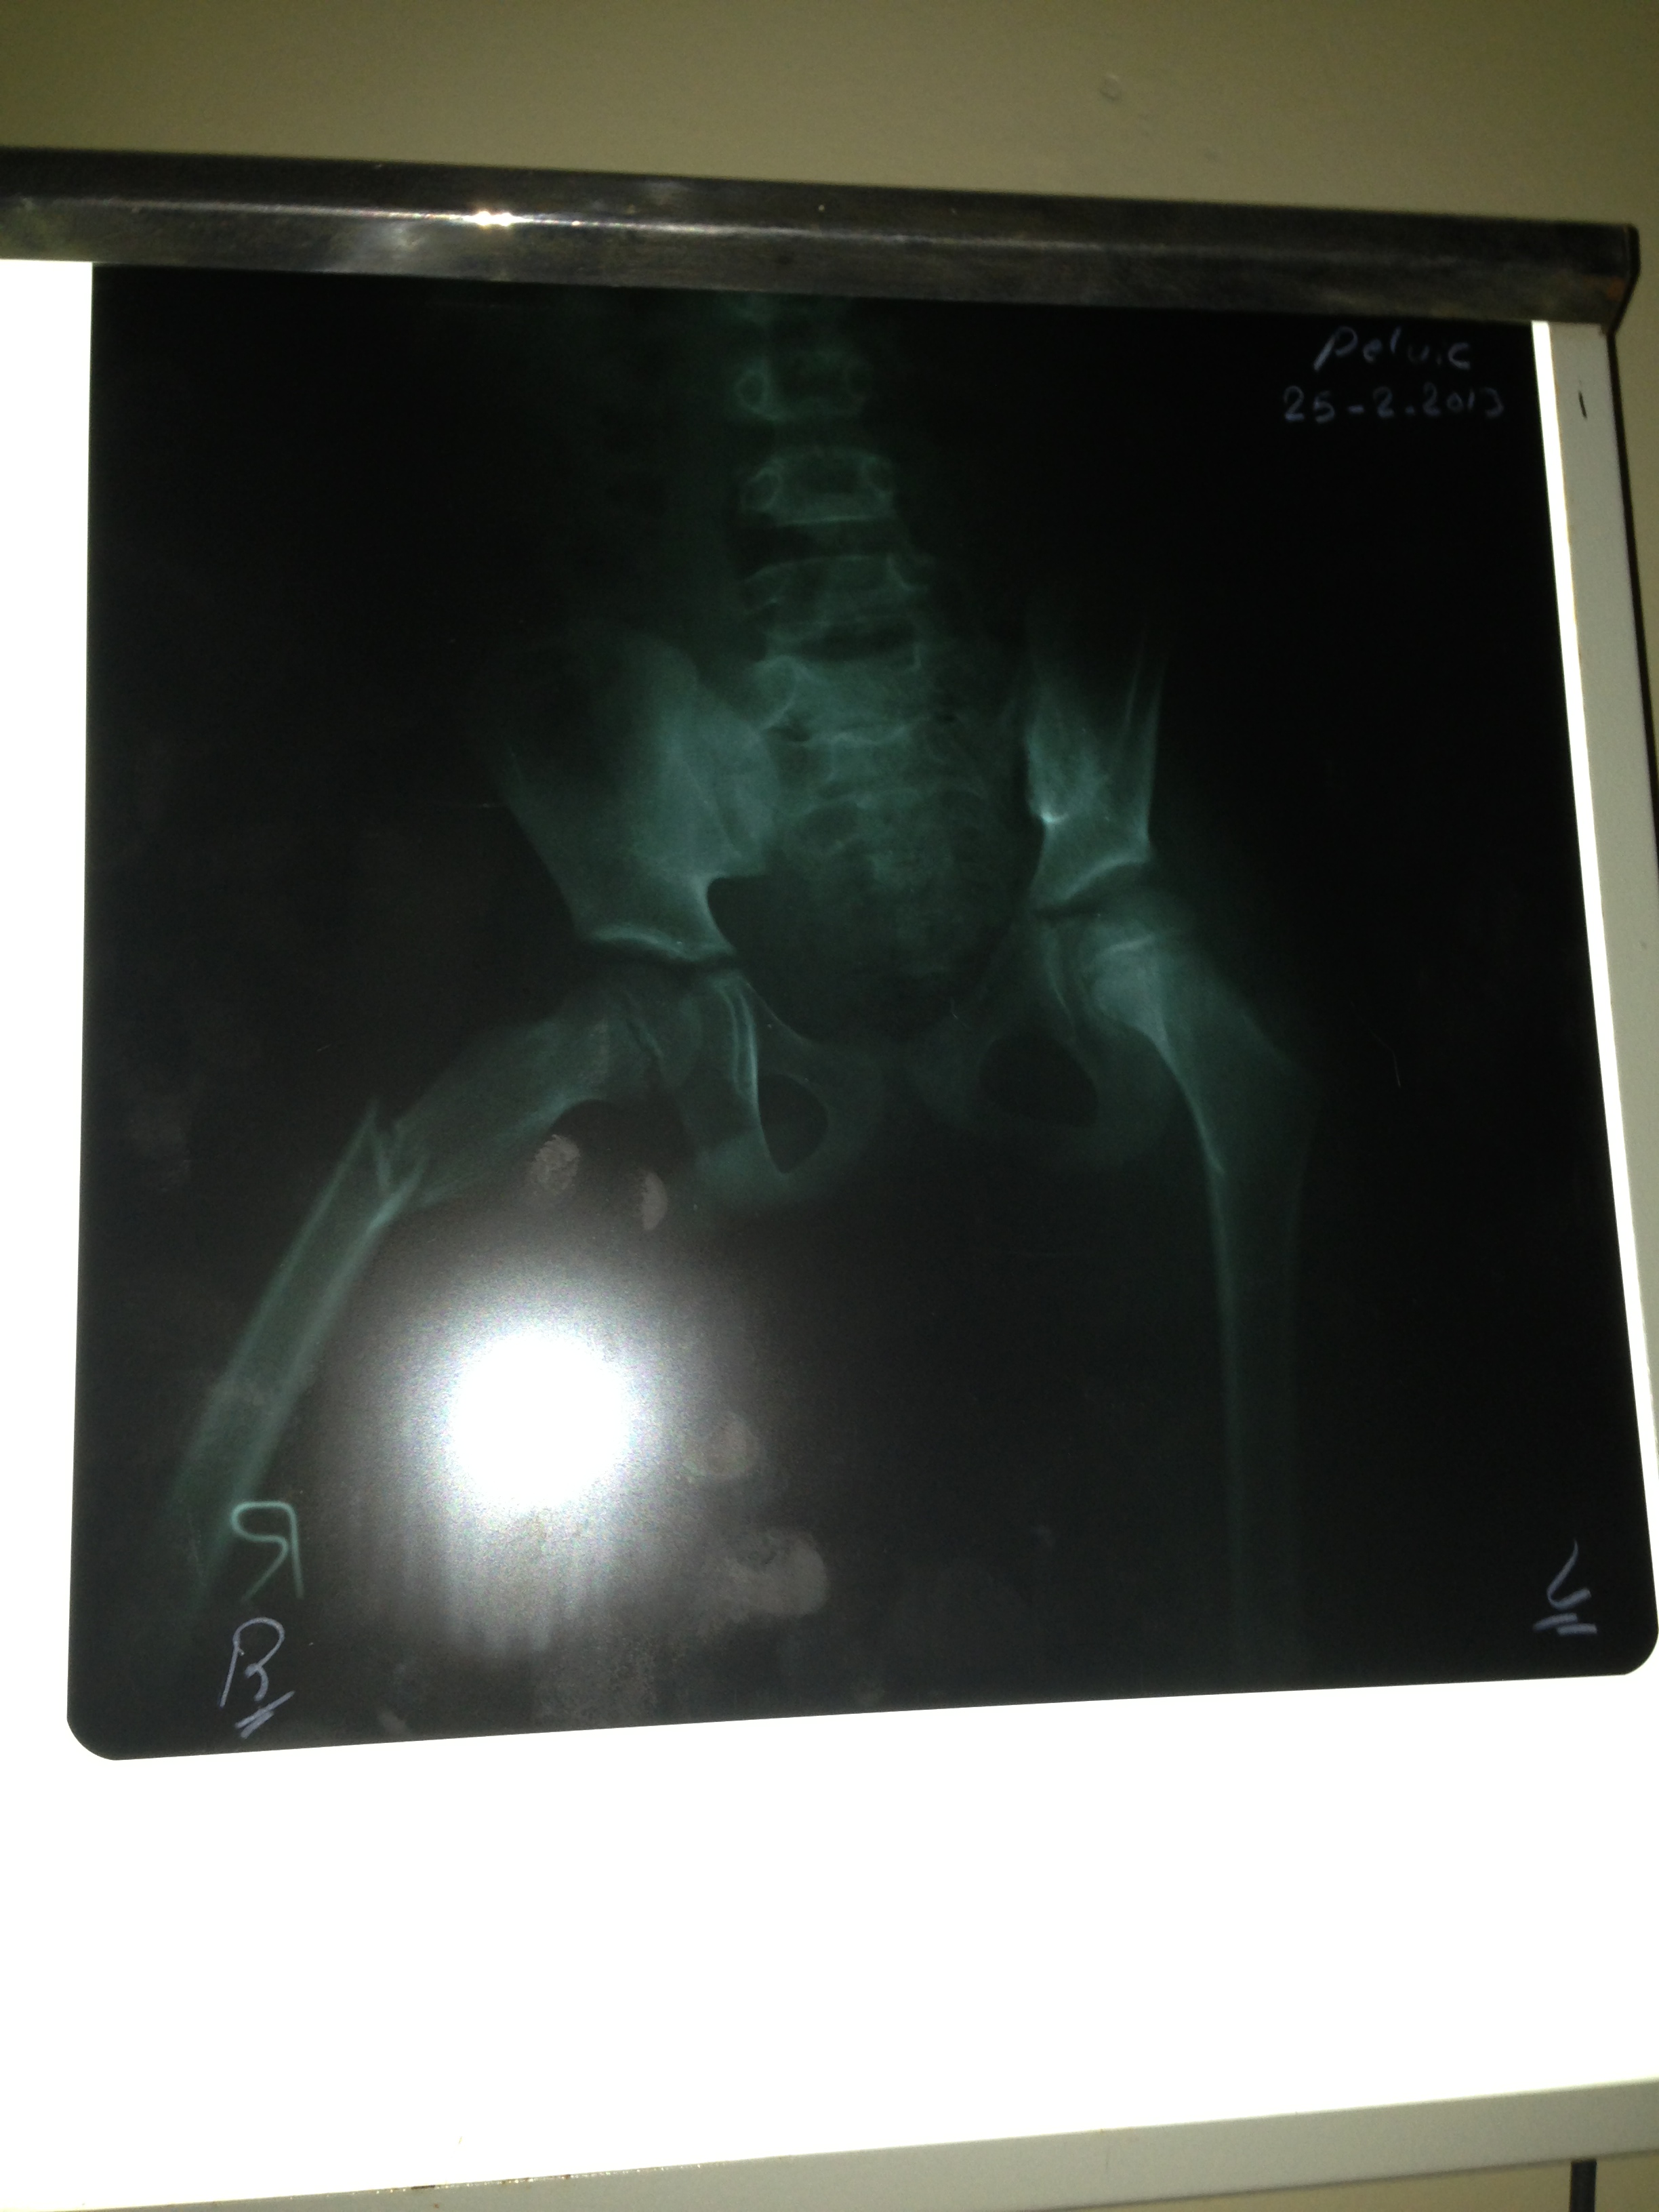

كسر في الورك